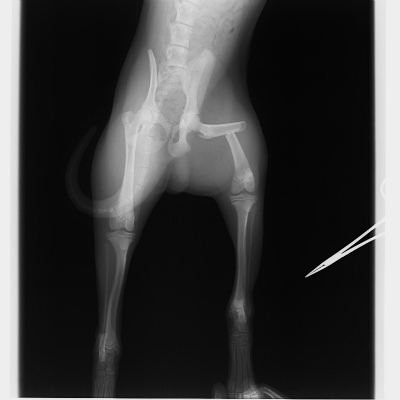

次に紹介する写真は、落下して起きてしまった大腿骨(ふとももの骨)の骨折です。

こちらも骨折用の金属プレートを用いて手術を行いました。